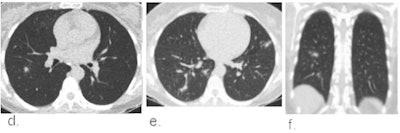

Example chest CT scans of a patient with a true-positive CO-RADS 4 score. (a,b) Two axial slices and (c) a coronal slice of a 79-year-old female with nine days of symptoms. CT shows diffuse ground-glass opacities close to visceral pleural surfaces but superimposed on emphysematous changes. Also note the widened esophagus. COVID-19 was RT-PCR confirmed. Images courtesy of the RSNA. Example chest CT scans of a patient with a false-positive CO-RADS 4 score. (d, e) Two axial slices and (f) a coronal slice of a 51-year-old female with two days of symptoms. CT shows bilateral multifocal areas of consolidation with halo and subtle areas of ground glass without contact to visceral pleural surfaces. RT-PCR for SARS-CoV2 was repeatedly negative and an alternative diagnosis was established with a blood culture-confirmed line sepsis. Images and caption courtesy of the RSNA.

Example chest CT scans of a patient with a false-positive CO-RADS 4 score. (d, e) Two axial slices and (f) a coronal slice of a 51-year-old female with two days of symptoms. CT shows bilateral multifocal areas of consolidation with halo and subtle areas of ground glass without contact to visceral pleural surfaces. RT-PCR for SARS-CoV2 was repeatedly negative and an alternative diagnosis was established with a blood culture-confirmed line sepsis. Images and caption courtesy of the RSNA.The study included 1,070 patients who presented in the emergency departments of six Dutch medical centers between March and April. Chest CT exams were scored using CO-RADS and the scores compared with RT-PCR results and a clinical reference standard that included factors such as COVID-19 contact history, oxygen therapy, and the timing of RT-PCR testing. The investigators rated CT's performance using receiver operating characteristics curve (AUC) analysis and odds ratios; they also considered the timing of patients' symptoms (from less than 48 hours to more than seven days).